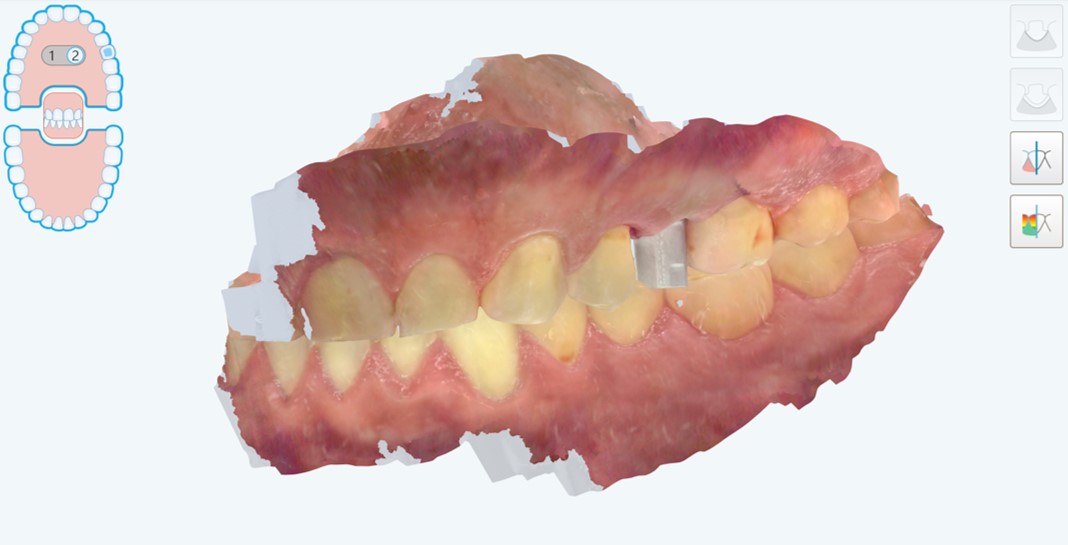

Presentiamo un caso di riabilitazione di edentulia singola attraverso una corona supportata da impianto prodotto con moderna tecnologia di laser sintering. Il paziente, maschio di 45 anni senza particolari problemi di salute generale, con una buona salute orale, fumatore ma non bruxista, si presentava alla nostra attenzione per la risoluzione di un problema di edentulia singola a carico dell’elemento #25 (secondo premolare superiore di sinistra) (Fig. 1,2).

Situazione pre-operatoria, visione laterale

Fig. 1. Situazione pre-operatoria, visione laterale.